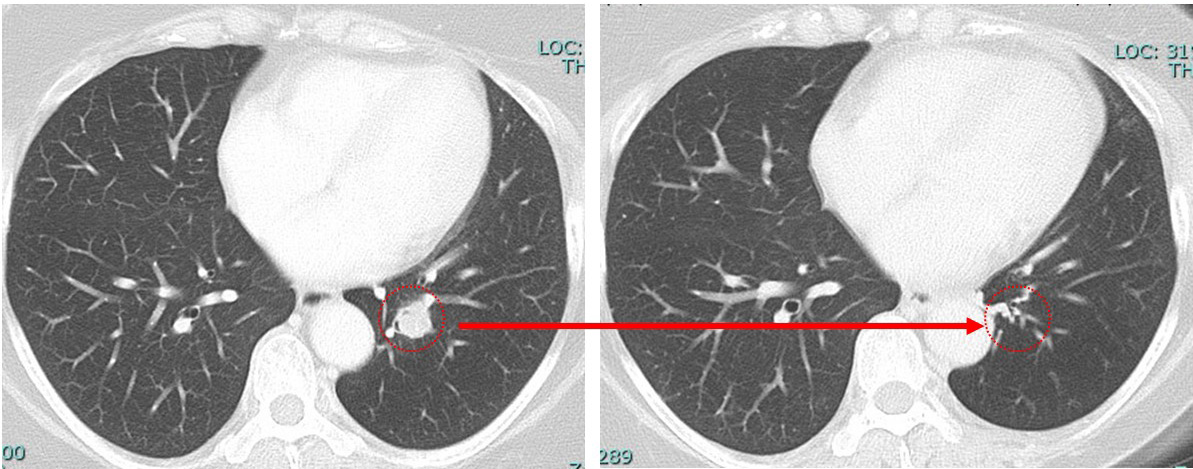

肺 かなり効いている

肺転移は(分子標的薬だけで)コントロールされている。

①「多発肺転移」は画像上かなり小さくなっているのに「胸の腫瘍は小さくならない」

anthracyclin終了時の時点でのCTでcCR

病変が(少なくとも)画像上消失した状態。